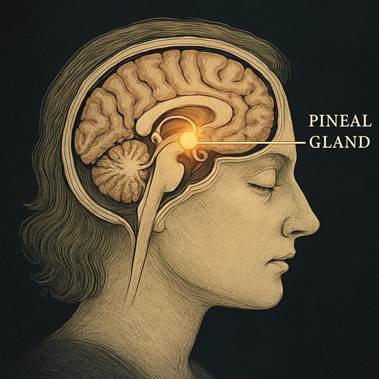

Pineal Gland Calcification:

The pineal gland is particularly vulnerable to calcification from aluminium and other environmental toxins. Disruption of pineal function impairs melatonin production, sleep regulation, and circadian rhythm entrainment (Kunz et al., 1999).

Pineal Gland and Circadian Disruption:

Accumulation of metals such as aluminium in the pineal gland impairs melatonin production and circadian rhythm regulation, contributing to sleep disorders, mood dysregulation, and broader systemic metabolic disturbances (Kunz et al., 1999).